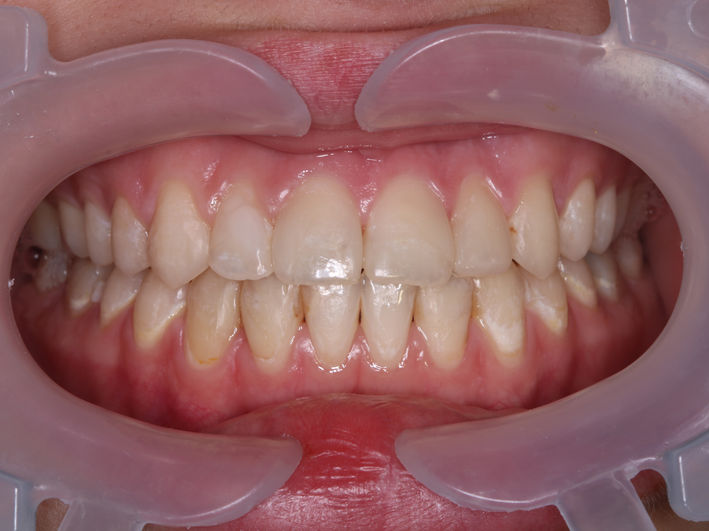

4. Tratament ortodontic pacient adult

O perioadă a existat preconcepția că tratamentul ortodontic este destinat doar copiilor sau adolescenților. Acest lucru nu este adevărat, putând fi realizat la orice vârstă. Particularitatea tratamentelor la pacienții adulți vine din prezența celorlalte patologii dentare și necesitatea colaborării cu celelalte discipline (chirurgie, parodontologie, endodonție, protetică).

În acest caz am realizat retratament endodontic 2.6, extracție 4.6, tratament ortodontic, inserare implanturi în locul dinților lipsă 1.6, 3.6, 4.6, coroane dentare din zirconiu multilayer înșurubate pe implanturi.